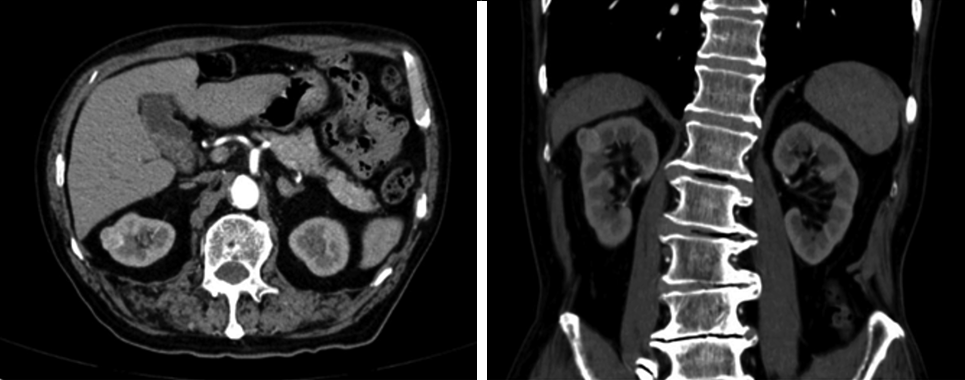

所有患者入院后完善血常规、肾功能、肿瘤指标、心电图等术前检查,术前均行泌尿系统超声、肾脏血管造影或增强MRI检查,明确肿瘤大小、位置、肾血管及腹腔淋巴结情况(图1)。

动脉期明显不均匀强化,考虑肾癌可能性大。双肾动脉双支型。周围脂肪间隙清晰,未见明显肿大淋巴结